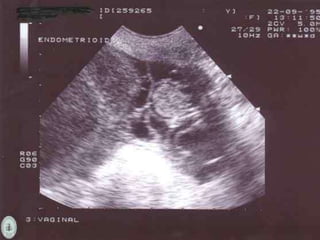

Tumores endometrioides

Imagenología

 Ecografía

 Tumores malignos: Multiloculados, sólidos ó ecogénicos,

mayores de 5cm, tabiques gruesos con áreas de

nodularidad.

20% de todoslos carcinomas de ovario. Mayormente son de tipo maligno. 40% de las veces es bilateral. Cursan con cáncer de endometrio. Áreas sólidas – Áreas quísticas. Tumores endometrioides

• #26 Sólidos, contienen zonas líquidas o necróticas.

• #27 Carcinoma endometrioide